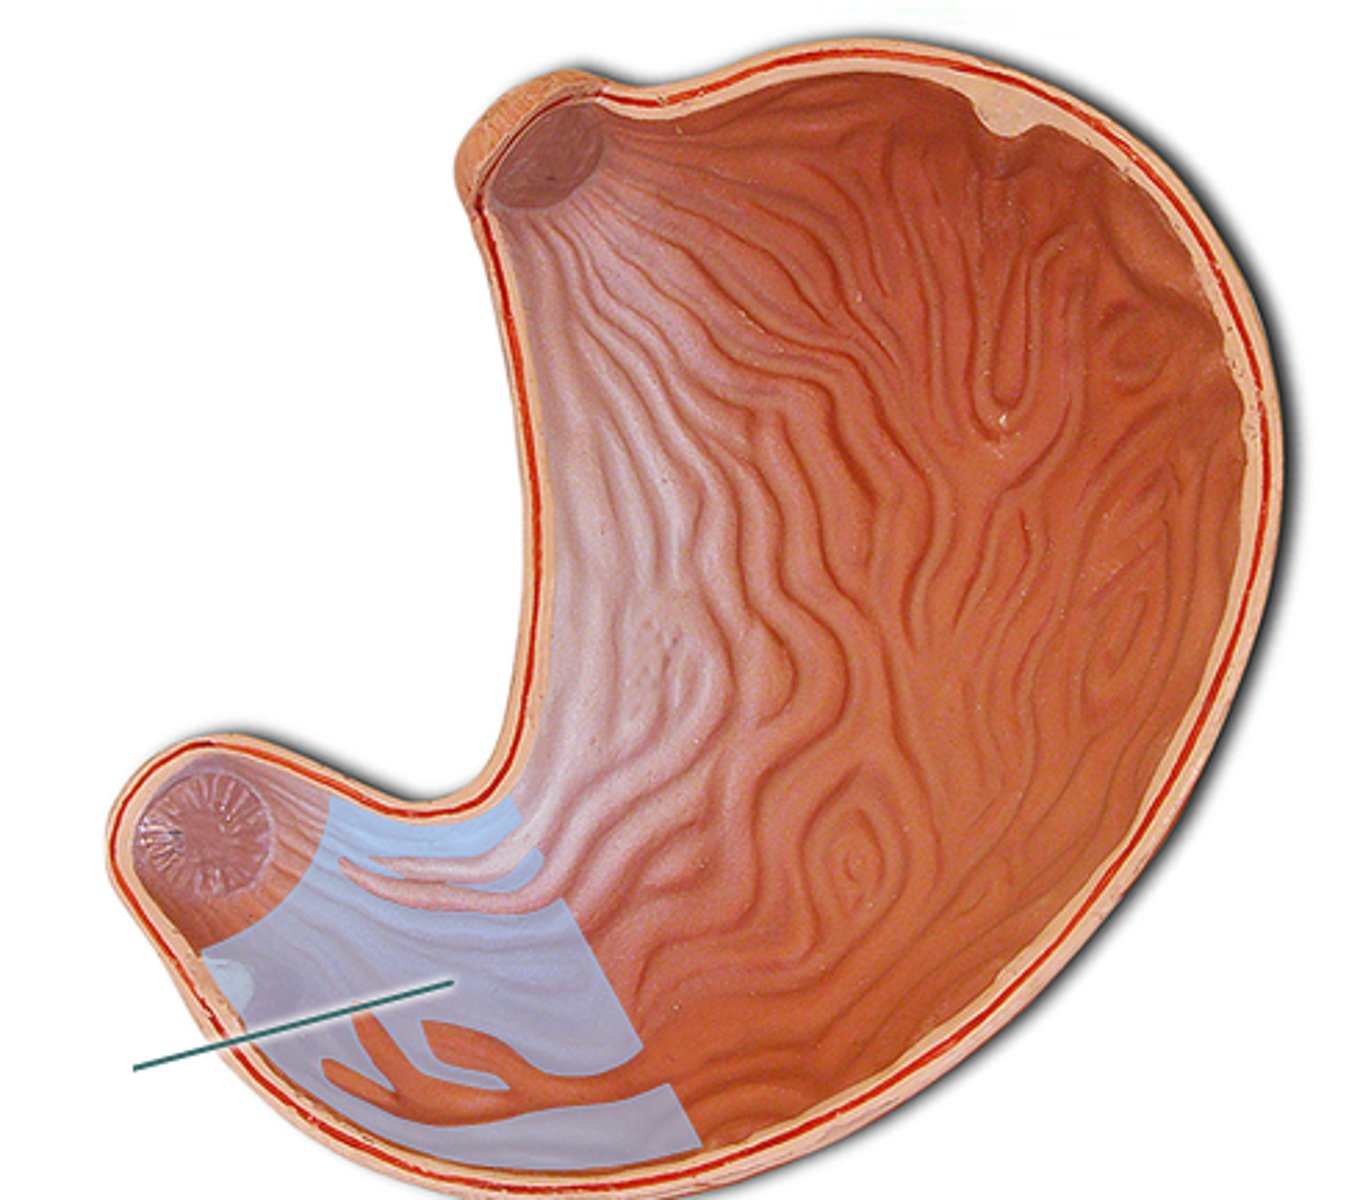

cardiac stomach (histology)

simple columnar epithelium

what kind of epithelium lines the mucosa of the cardiac stomach?

gastric pit (cardiac stomach)

lumen (cardiac stomach)

mucosa (cardiac stomach)

mucosal epithelium (cardiac stomach)

lamina propria (cardiac stomach)

muscularis mucosa (cardiac stomach)

submucosa (cardiac stomach)

contains glands and blood supply

muscularis externa (cardiac stomach)

serosa/adventitia (cardiac stomach)

stomach

cardia

fundus (stomach)

body (stomach)

pylorus

pyloric sphincter